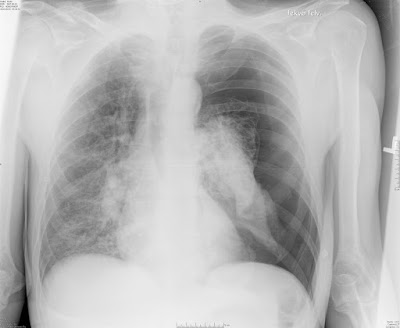

Hirtelen kezdődött mellkasi fájdalom a bal oldalon. Az előzményben korábbi PTX, bullák nincsenek.

- Pneumothorax